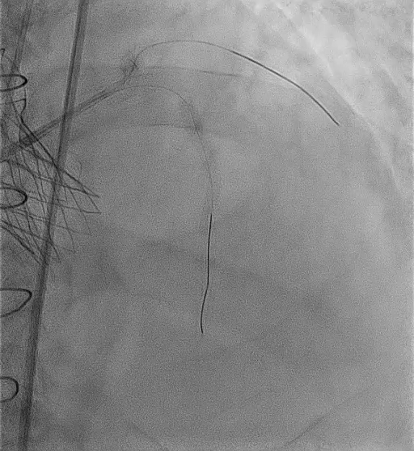

SEV 24 mm was chosen based on CT measurement and bifemoral access was obtained. Carotid filter was placed for cerebral protection.During resheathing of the valve there was sudden circulatory collapse. CPR started and left coronary catheterisation revealed occlusion of left main. Flow was established in LAD with immediate wiring and ballooning. Finally TAVR valve was deployed after LAD flow was established.LCX flow was then resolved and LM bifurcation PCI was done using crush technique Patient was finally discharged in hemodynamically stable condition.